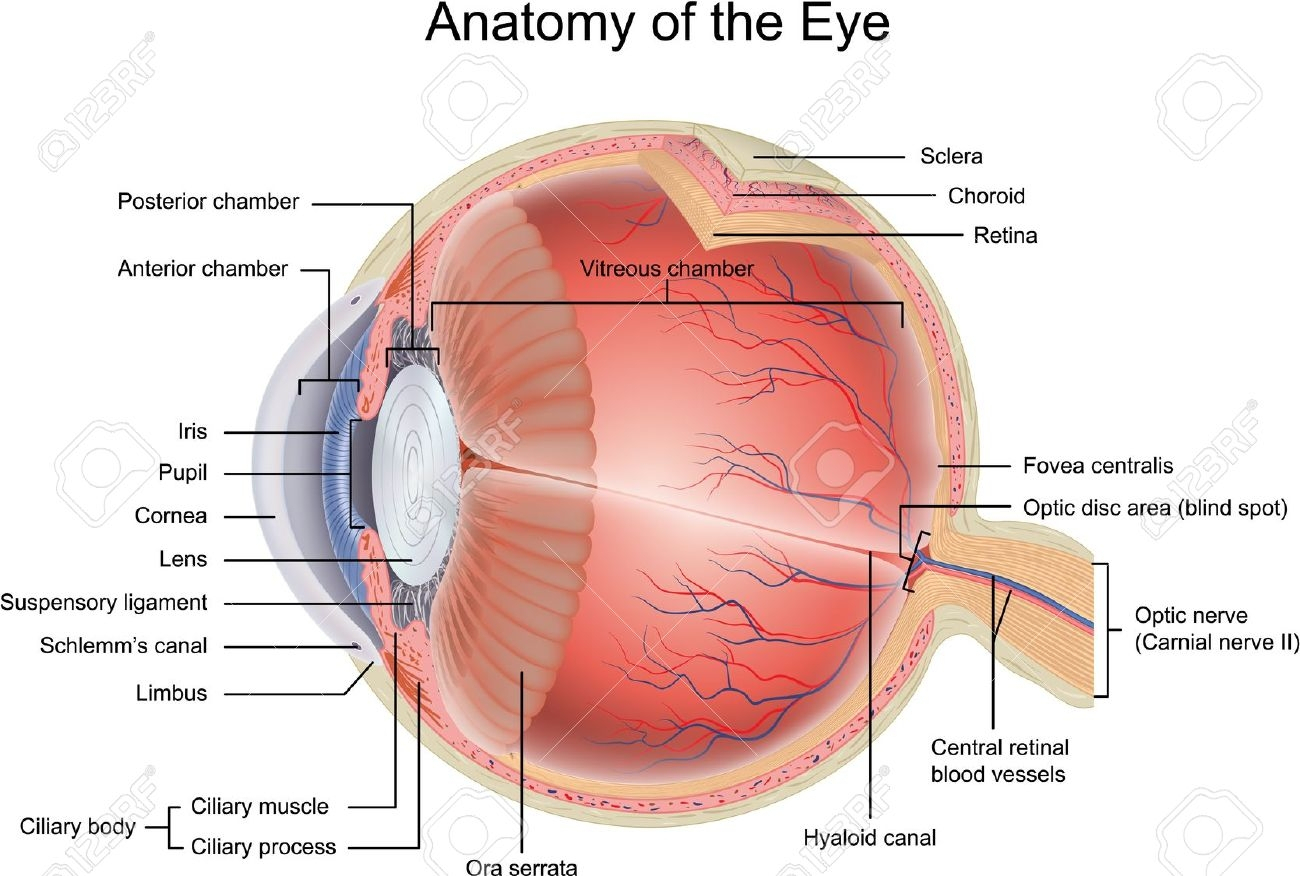

The Structure of the Eyes

The Structure of the Eyes

The eye is made up of different parts. Each part performs different roles in helping us to see. The parts of the eyes are: Iris, Cornea, Lens, Retina, Optic nerve, Pupil, Tear gland, the eye ball, Eyebrow, Eyelashes, Aqueous and Vitreous humors.

PARTS OF THE EYES FUNCTIONS

The Iris ---- This is the coloured part of the eye. It surrounds the pupils and helps it to regulate the pupils to darken or brighten.

Cornea- ----The cornea is a protective layer. It helps to keep dirt and dust away from the pupils.

Lens ----- This is the glass-like part of the eyes. It helps the eyes to see things that are so far or nearby changing their size.

Pupils- ----This is the hole in front of the eyeball through which light enters the eyes.

Optic nerve ----- This part of the eye is a sensory nerve, which links the eyeball to the brain.

Retina ----- This is a sensitive spot in the eye where images are formed.

Tear gland- ---- This gland helps to pour out tear over the front of the eye. The tears poured out, helps to wash away dusts, which enters the eyes.

Eyes lashes- ---- These are the hair at the lid. They help to protect the eye from dirt and dust.

The eye balls- ---- These are the organs of sight connected to the brain through the optic nerve.

Eye lid ----- This is the skin covering the eyeball. It can be closed to prevent foreign objects from entering the eyes.

Generally, the eye helps us to see.